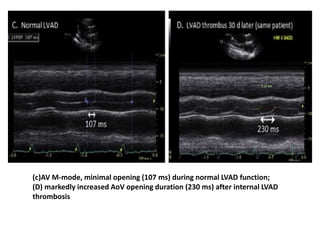

increased LVIDd after LVAD thrombosis

(c)AV M-mode, minimal opening (107 ms) during normal LVAD function;

(D) markedly increased AoV opening duration (230 ms) after internal LVAD

thrombosis

increased LVIDd afterLVAD thrombosis

(c)AV M-mode, minimalopening (107 ms) during normal LVAD function; (D) markedly increased AoV opening duration (230 ms) after internal LVAD thrombosis